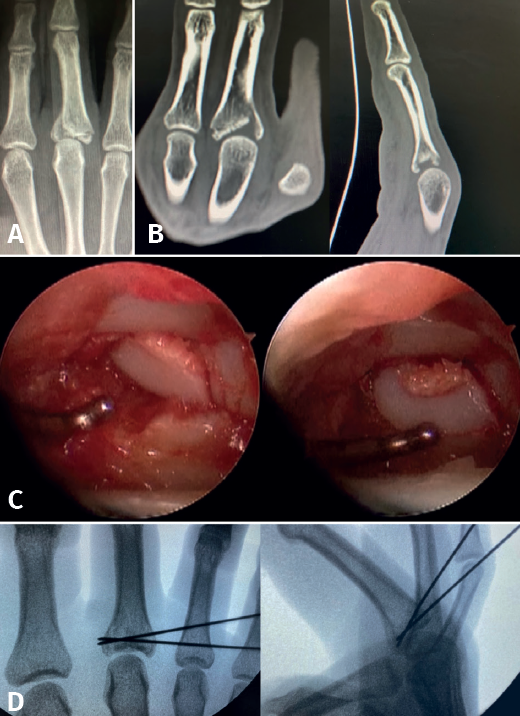

- Fractures with avulsion of the insertion of the collateral ligament (Figures 2 and 3).

The clearest indication is axial compression fractures resulting in central joint collapse, predominantly at the base of the proximal phalanx.

The main fragments are reduced with the aid of a palpator or a small blunt dissector. External reduction of the fragments may be necessary, especially when they are impacted in the centre of the articular surface. This is especially common at the base of the proximal phalanx. To do this, we introduce a 1.0 Kirschner wire through the fracture site, through an extra-articular "window", and in "joystick" fashion, we lower the impacted fragment. Sometimes it is advisable to check each of the maneuvers using fluoroscopy, which can be positioned perpendicular to the arm or in the traditional manner, which requires us to release the hand of the patient in order to perform the check.

In some cases it is necessary to insert a spongy graft through the fracture site to maintain reduction and thus avoid joint step-off.

Once the fragments have been reduced, 0.8 or 1.0 Kirschner wires are used to maintain reduction (Figure 7). Sometimes we can only maintain reduction by applying a stop, to prevent the osteochondral fragment from collapsing. Depending on the fracture pattern and the surgeon's preference, we can use conventional screws, cannulated screws, etc. (Figures 8 and 9).